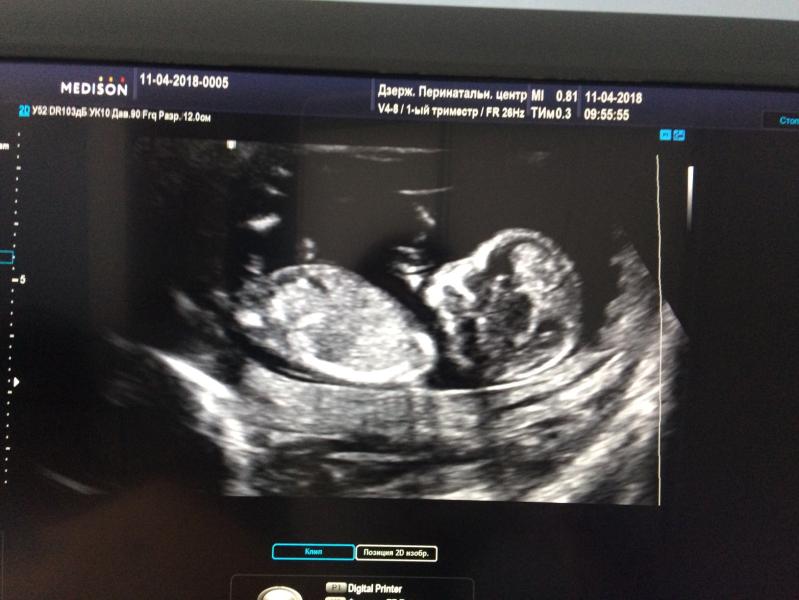

Первый мой скрининг)) Наконец-то увидела мою ляльку😘 Самый любимый человек на земле😍💋 Моё счастье❤️🌺

Не слышали про половой бугорок?) я тут начиталась про него, скоро сама на скрининг, по вашей фотографии мне кажется что девочка, но это чисто мое предположение)

Пол сказали???))) мне через недельку 😃 нам сегодня 12)